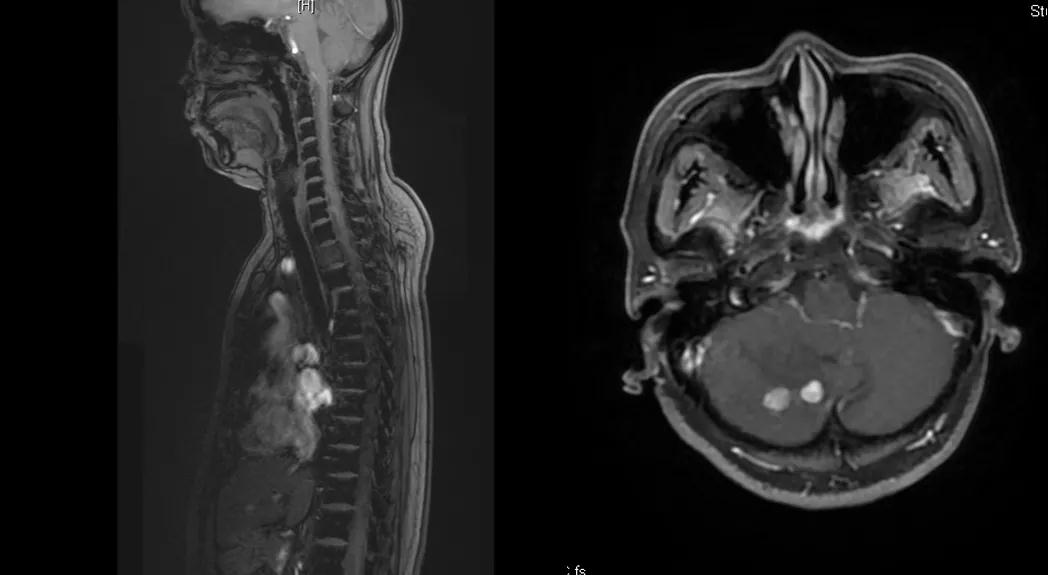

曲妥珠单抗辅助治疗结束6个月后,患者出现左侧胸部疼痛,ECT检查提示:左侧第4、5肋骨及T2胸椎转移;MR提示:T2椎体转移,肝S6段异常强化灶,考虑转移瘤可能性大;脑转移(图1)。

给予T-DM1治疗。治疗6个月后复查MR显示脑、肝、骨转移瘤均较前明显缩小,达到部分缓解(PR)(图2)。目前PFS已达10+个月。

图2

患者为ⅢA期(cT3N1M0)、三阳性乳腺癌,经AC-TH新辅助治疗达到降期(ypT2N0M0)。患者内分泌+抗HER2辅助治疗结束6个月时出现转移进展(脑、肝、骨),给予THP一线治疗,因无法耐受毒副作用而改为T-DM1,治疗6个月达到肝、脑、骨转移PR,患者目前中位PFS已超过10个月,T-DM1治疗过程中仅出现轻度CIT,且可自行恢复。